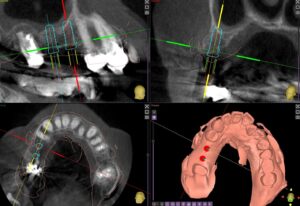

70代男性右の上下にロングスパンのブリッジが入っています。しばらくはそのまま定期検診を行っていましたが、右上7の根尖病巣に痛みを生じ、同じようにブリッジをすると負担がかかりますので、右上65にインプラント埋入を計画しました。

コンピュータガイドでしっかり位置決めを行います。やや上顎洞にかかるのでソケットリフトという手術を併用しました

しっかりと歯が入りました。その後右下も希望されたため右下にもインプラントを行いました。